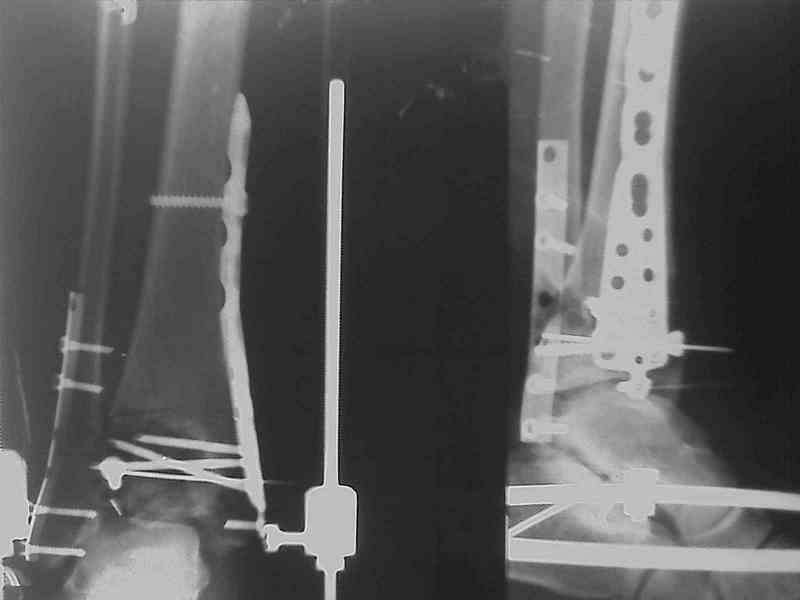

Яков изложил все необходимые аспекты лечения переломов пилона, и, не желая менять тему, решил выставить нашу точку зрения в двух клинических примерах.

При лечении внутрисуставных переломов типа "Pilon"

или "Tibial Plateau" на голени, применение простых

наружных фиксаторов типа "Spanning ExFix" или "Travelling ExFix" стал одним из стандартом этапного лечения.

В первые часы после поступления больным экстренно накладывается простой фиксатор из двух поперечно проведенных стержней или сооружается "Delta

Frame" в зависимости от места локализации, и проводится дистракция.

Здесь выставлена пара случаев перелома пилона, оба

случая леченные этапным наружным фиксатором.

Второй случай фиксирован аппаратом Илизарова.